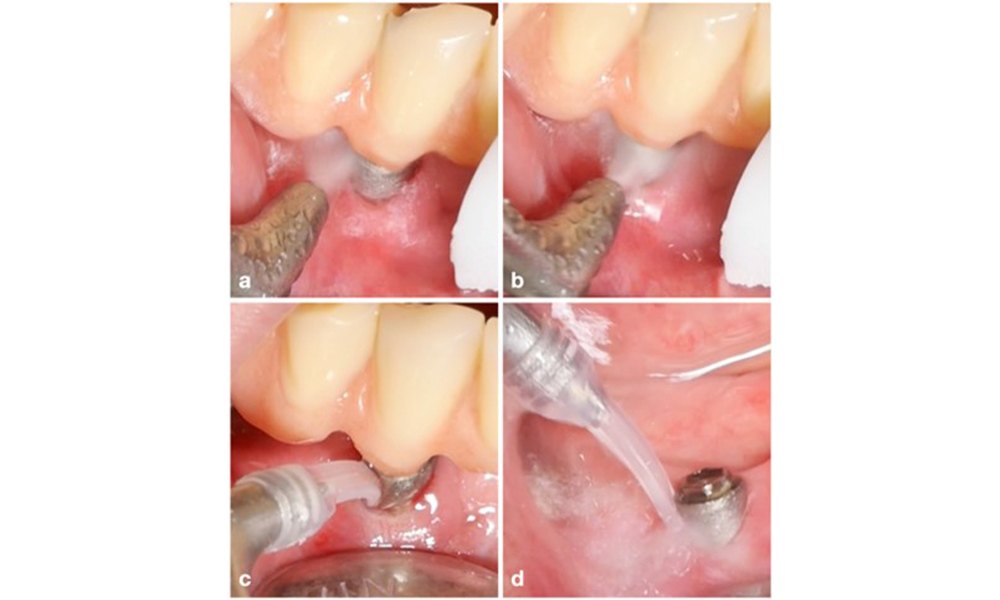

Le choix de l'équipement dépend des circonstances cliniques, comme la distinction entre le tartre et la plaque molle. Ainsi, en cas de tartre, il convient d'utiliser d'abord des curettes en titane ou en plastique, ou des embouts spécialement conçus pour les détartreurs à ultrasons, puis un appareil d'aéropolissage (figure 7). Dans les cas où il n'y a qu'une accumulation de plaque molle, un dispositif d'aéropolissage peut suffire. Les dispositifs d'aéropolissage sont faciles à utiliser pour l'opérateur et le patient et sont au moins aussi efficaces que les instruments standard (Schwarz et al. 2015a).

Patient présentant une mucosite péri-implantaire, une mauvaise hygiène bucco-dentaire et une accumulation de tartre (a). Dans ce cas, il est conseillé de combiner différents équipements : des embouts spécialement conçus pour les détartreurs à ultrasons sont nécessaires pour éliminer le tartre (b), et un dispositif d'aéropolissage permet d'éliminer le biofilm mou restant (c-d).